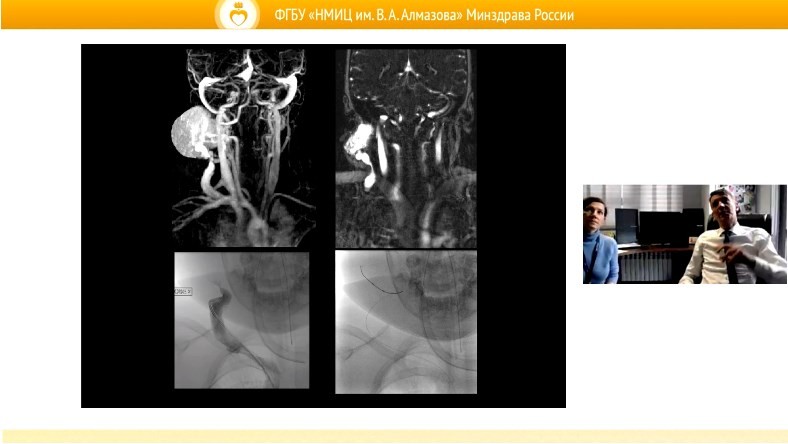

На мероприятии докладчики поделились опытом использования различных тактик и способов обследования, включая современные методы визуализации, морфологическую и молекулярно-генетическую диагностику. Подробно обсуждались вопросы использования таргетной терапии у детей с различными нозологическими формами сосудистых опухолей и мальформаций.

В ходе конференции участники представили коллегам сложные клинические случаи, потребовавшие больших усилий как при верификации диагноза, так и длительных периодов терапии с комбинацией различных методов. Сосудистые хирурги рассказали о возможностях малоинвазивной хирургии у детей при обсуждаемой патологии.